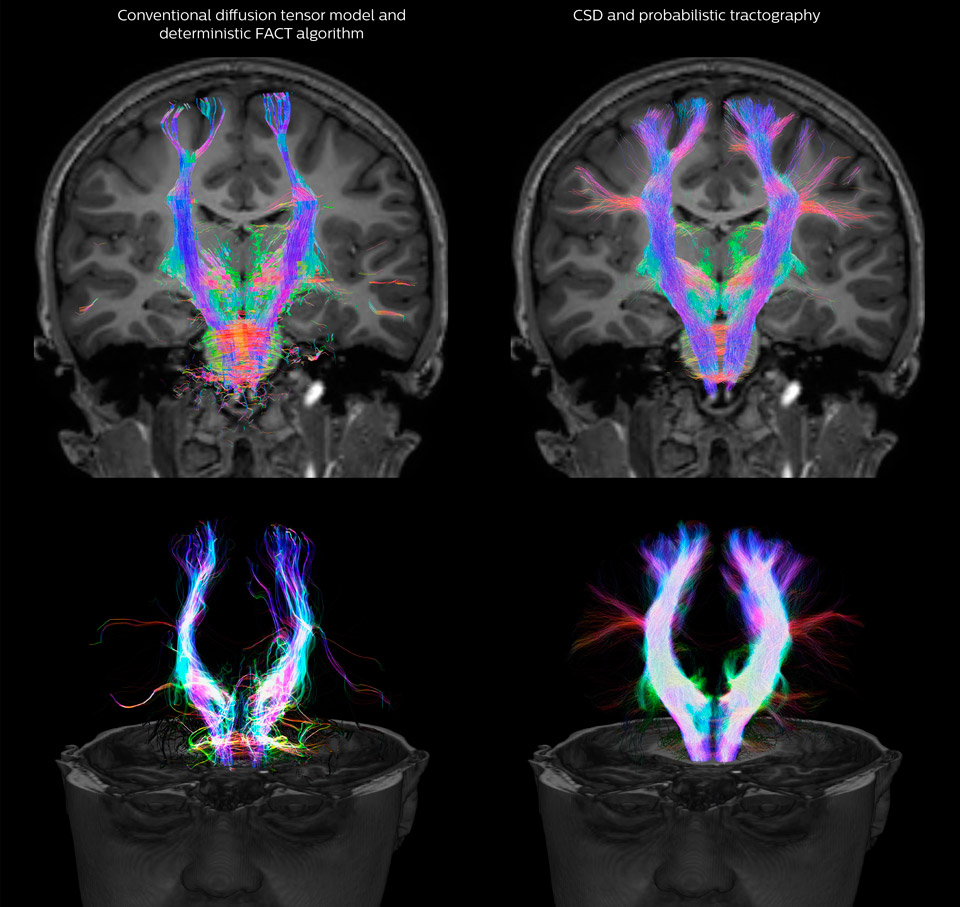

Fiber tractography of the corticospinal tract with seed region of the posterior limb of the internal capsule. Different processing based on the same data.

All images were created from the same acquisition in a child using Ingenia 3.0T CX and 32-channel dS Head coil. Diffusion data was acquired at b-values 0, 500, 1000, 2000, 3000. The use of high b-values (3000 s/mm2) effectively suppresses extra-axonal water signal and provides high angular resolution.

CSD of multishell DWI results in the white matter FOD at each voxel. Unlike the conventional diffusion tensor model, this approach enables accurate modeling of multiple fiber populations within a single voxel.